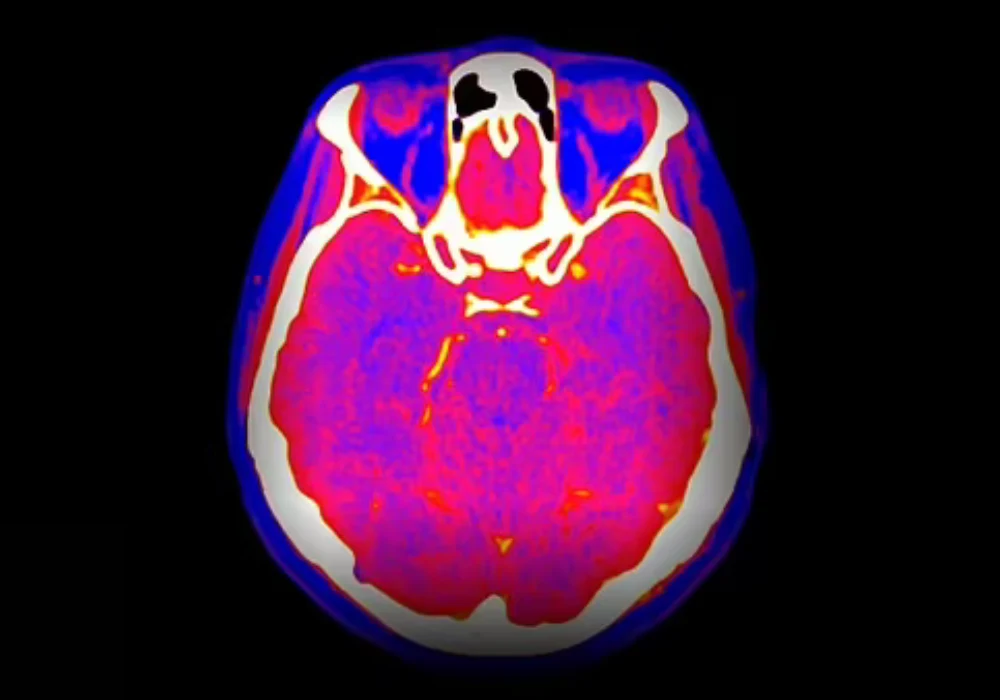

Spectral computed tomography (CT) is increasingly available across healthcare systems, offering energy-resolved information that can refine tissue characterisation and support quantitative assessment. Despite this growing access, consistent day-to-day use remains limited and quality assurance (QA) practices vary widely. A global survey coordinated by the International Atomic Energy Agency documented current availability, utilisation, QA and training patterns, highlighting progress alongside persistent barriers. The responses, gathered between October 2024 and June 2025 from institutions across multiple regions, indicate rapid modernisation of CT fleets, expanding clinical applications and uneven integration into routine workflows. Training gaps, especially for medical physicists and heterogeneous QA approaches were recurrent themes, pointing to the need for clearer guidance, aligned protocols and targeted capacity building to translate capability into consistent practice.

Reported applications were diverse, spanning cardiology, abdominal and pancreatic imaging, urology, musculoskeletal assessment, neurological indications and oncology. Common use cases included pulmonary embolism assessment, particularly where contrast load must be minimised, abdominal lesion characterisation, perfusion evaluation, low-contrast-dose scenarios and kidney stone analysis with differentiation of uric acid and calcium composition. Cardiac planning and other cardiac imaging tasks featured in several responses. Functional tools such as virtual non-contrast imaging, metal artefact reduction, iodine mapping and interventional planning were also noted. Some centres applied spectral modes broadly across most protocols, while others reserved them for narrow indications or reduced use due to operational constraints.